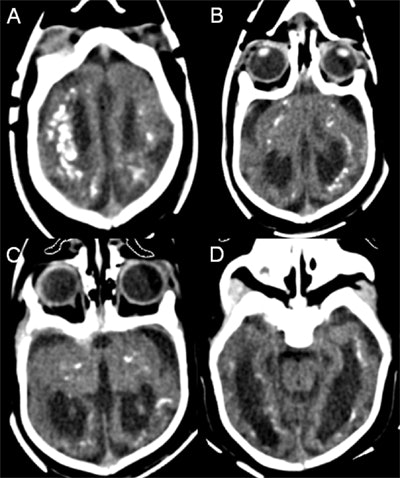

The group reported what appeared to be the effects of the Zika virus on brain anatomy, as seen in head CT images of 23 infants, obtained at a mean age of 36 days after birth (range, 3 days to 5 months). Intracranial calcifications were seen in all of the infants and mainly involved the frontal lobe (in 69% to 78% of the infants) and the parietal lobe (in 83% to 87%).

The calcifications were mostly punctate (72% to 100%) in configuration, with a predominantly band-like distribution in 56% to 75%. Calcifications were found in the basal ganglia (57% to 65%) and in the thalamus (39% to 43%), the authors wrote.

Ventriculomegaly was seen in all of the infants and was rated as severe in the majority (53%), but it involved only the lateral ventricles in 43%. In addition, all infants had global hypogyration of the cerebral cortex, which was severe in 78%.

Cerebellar hypoplasia was present in 17 cases (74%) and involved only one cerebellar hemisphere in three infants. In two infants, the brainstem was globally hypoplastic. All infants showed abnormal hypodensity of the white matter, and in 87% it diffusely involved all of the cerebral lobes. One infant demonstrated chronic encephalomalacic changes from ischemic stroke in the vascular territory of the left middle cerebral artery.

Intrauterine infection with the Zika virus appears to be associated with severe brain anomalies, including calcifications, cortical hypogyration, ventriculomegaly, and white-matter abnormalities, though it's uncertain when exactly the infection may have occurred in these infants, the authors concluded.